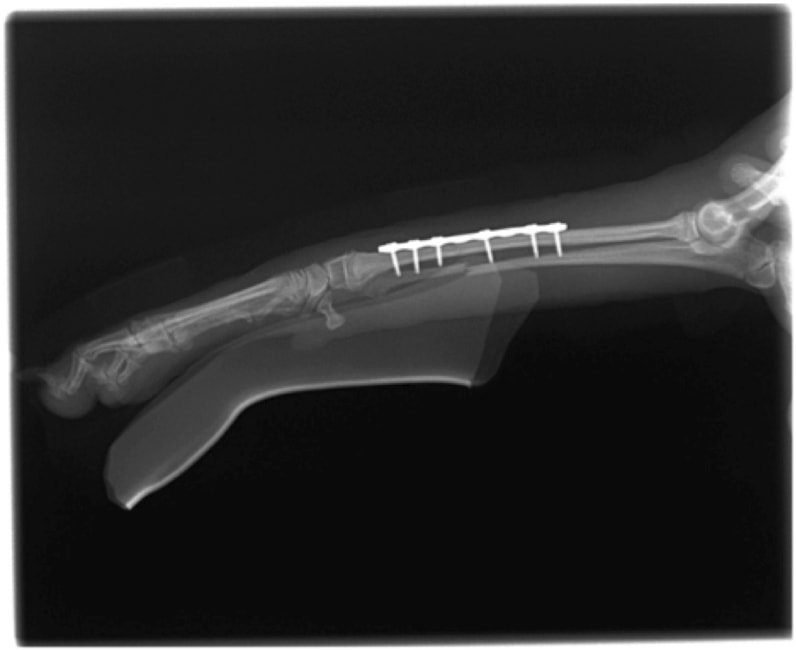

ペルシャ猫 11ヶ月齢 雄

他院にて左大腿骨遠位の成長板骨折(salter-harrisⅠ型)が認められており、治療相談を目的として来院。当院にて、キルシュナーワイヤーを用いたピンニングにより骨折部位の整復を行いました。術後の経過は良好で、現在も経過観察中です。

術後レントゲン

機器

Arthrex社のターゲティングデバイスを用いてピンニングの位置を調整することで、確実な固定を行っています。当院ではこの手術器具以外にも、人の手術にも使用される様々な器具を導入し、手術精度を高め、また医療メーカーと新しい器具の開発、試作にも取り組んでおります。